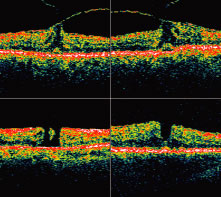

Soon after, spontaneous vitreofoveal separation may occur. The contracted prefoveolar vitreous cortex (now detached from the underlying retina) may become visible as a semitranslucent prehole opacity (pseudo-operculum) lying anterior to a small foveolar hole. This condition is classified as a stage 2 full-thickness macular hole (Fig. 5). Centrifugal retraction of foveolar retinal receptors continues to enlarge the diameter of the hole; Gass suggested that any hole 400 μm or larger should be classified as a stage 3 macular hole (Fig. 6). After separation of the vitreous from the entire macula and optic disc, the hole is classified as stage 4, regardless of its diameter. Recently, the introduction of optical coherence tomography (OCT) has allowed researchers to study the exact relationship between the vitreous and fovea in the development of macular holes. OCT is analogous to ultrasound but measures optical, rather than acoustic, reflectivity (Fig. 7). The higher frequency of light waves compared with acoustic waves allows for a much higher longitudinal resolution (10 μm vs. 150 μm). OCT evidence suggests that in most macular holes, the first step is actually the formation of a foveal pseudocyst (splitting of the retina at the fovea). It is postulated that anterior tractional forces from the prefoveal vitreous cortex cause this pseudocyst to form. The anterior wall of this cyst serves as a flap in stage 2 holes and as an operculum in stage 3 holes.15,16 |

| Many macular lesions simulate macular holes or macular hole precursor lesions (stage 1A

biomicroscopic evaluation of the lesion.20 Clinical diagnostic tests for discriminating full-thickness macular holes